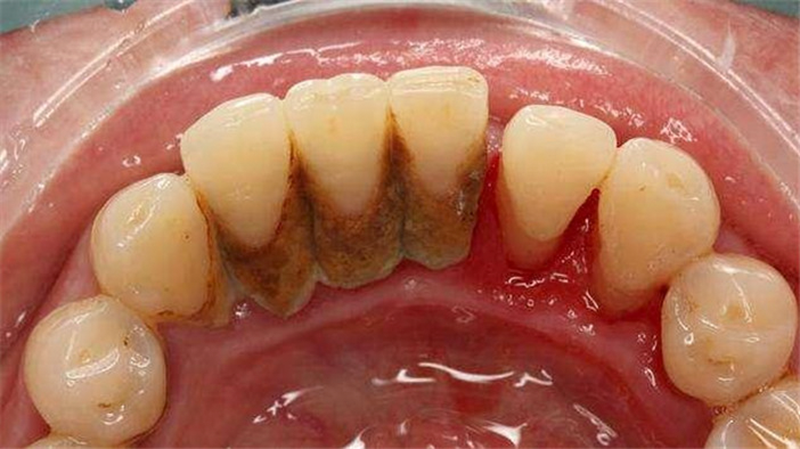

Quá trình vệ sinh răng miệng không kỹ càng, những vụn thức ăn sót lại sẽ kết hợp với vi khuẩn tạo thành mảng bám trên răng. Sau một thời gian mảng bám sẽ biến thành vôi răng bám chặt vào răng. Chỉ có thể loại bỏ khi tới nha khoa.

- Mất thẩm mỹ: Vôi răng xốp nên dễ bắt màu. Khi sử dụng những loại thực phẩm sậm màu hoặc uống trà, café hay hút thuốc, lớp vôi răng sẽ sậm màu rõ rệt.